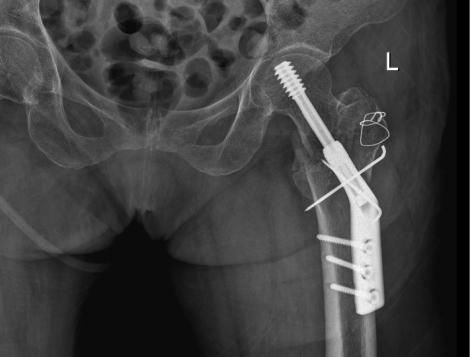

△術前

△術後

△術前

△術後

△術前

△術後